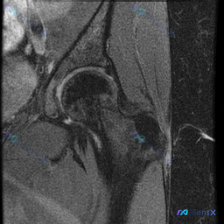

今天看到一份很典型的髋关节MRI病例,问题是「影像里可见的软组织液性成分是什么」,整理了完整的资料和分析思路,和大家分享讨论。 病例影像基本信息 这是一张髋关节矢状位T2加权MRI图像,核心观察结果如下: 1. 骨性结构:股骨头外形圆滑,无明显塌陷变形,软骨下骨板轮廓大致完整,未见骨质破坏 2. 关...